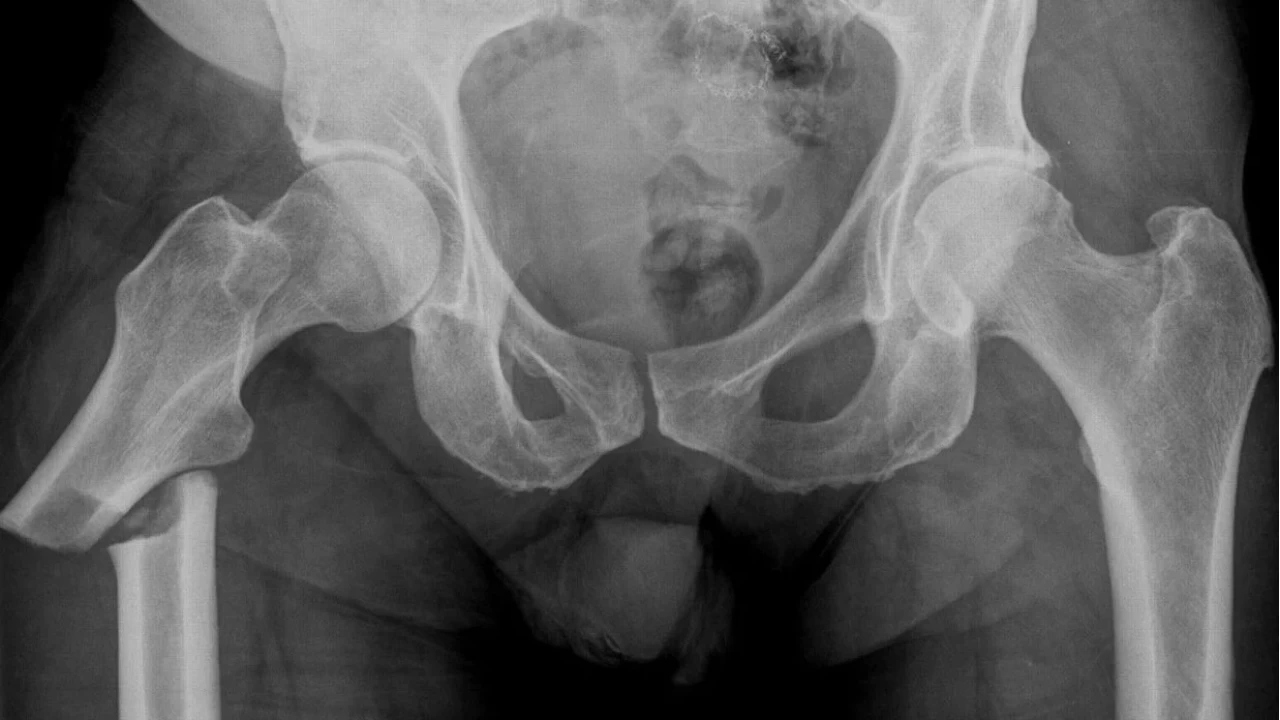

Kalça kırığı, uyluk kemiğinin (femur) kalça eklemine yakın kısmında meydana gelen bir kırılmadır. Genellikle düşük enerjili travmalar, örneğin ev içinde düşme gibi basit olaylar sonucu ortaya çıkar. Özellikle osteoporoz (kemik erimesi) olan bireylerde bu tür kırıkların oluşma riski çok daha yüksektir.